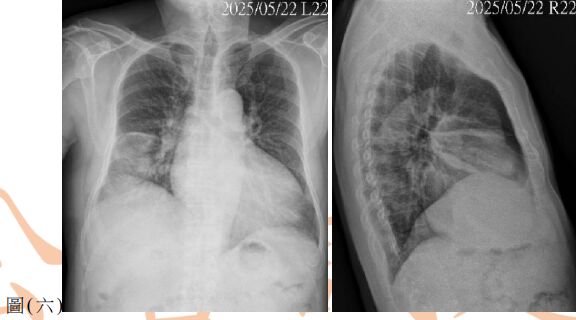

37. 病人因咳嗽、胸悶數週求診,無發燒,聽診無喘鳴音,血壓 150 / 88 mmHg,雙腳輕度凹陷性水腫,胸部X光如圖(六)。此病人的初步處置,下列何者最適當?

(A) 檢測腫瘤指數,安排電腦斷層導引切片檢查 (B) 痰液培養結核菌,給予抗結核藥物治療 (C) 先給予經驗性抗生素,一週後追蹤胸部X光 (D) 先給予利尿劑,一週後追蹤胸部X光